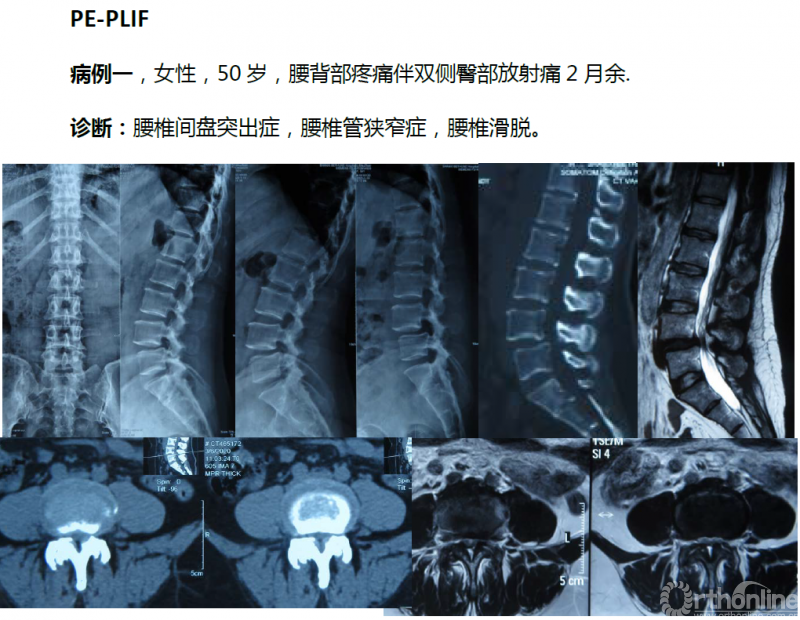

总的来说,单边双通道镜下融合技术和LUSTA大通道镜下融合技术对于解决腰椎间盘突出症、腰椎管狭窄症合并腰椎不稳以及Ⅱ°以内腰椎滑脱均有显著疗效,两种技术应该平行发展,两架马车应并驾齐驱共同前进。

病例分享:(滑动查看)